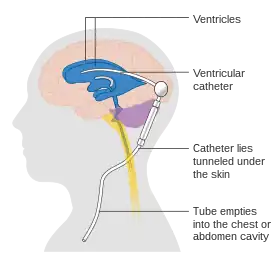

A diagram of a typical brain shunt | |

A cerebral shunt is a device permanently implanted inside the head and body to drain excess fluid away from the brain. They are commonly used to treat hydrocephalus, the swelling of the brain due to excess buildup of cerebrospinal fluid (CSF). If left unchecked, the excess CSF can lead to an increase in intracranial pressure (ICP), which can cause intracranial hematoma, cerebral edema, crushed brain tissue or herniation.[1] The drainage provided by a shunt can alleviate or prevent these problems in patients with hydrocephalus or related diseases.

Shunts come in a variety of forms, but most of them consist of a valve housing connected to a catheter, the lower end of which is usually placed in the peritoneal cavity. The main differences between shunts are usually in the materials used to construct them, the types of valve (if any) used, and whether the valve is programmable or not.[2]